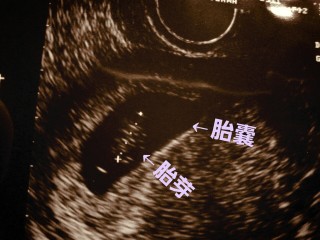

5週目の初診では見えなかった胎芽、2週間の間に11.0mmまで成長していて、ビックリだったけど、心拍も確認できて一安心です。

7w2d

やっと心拍が確認できました!

頭殿長13.9mm。